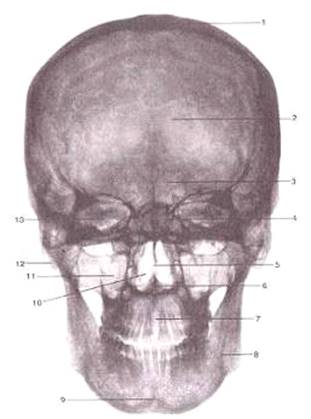

Вид спереди.

-крыша (свод) черепа;

-лобная кость;

-лобная пазуха;

-ячейки решетчатой кости;

-костная перегородка полости носа;

-передняя носовая ость;

-межверхнечелюстной шов;

-нижняя челюсть;

-подбородочный выступ;

-полость носа;

-верхнечелюстная пазуха;

-сосцевидный отросток;

-глазница.

На рентгенограмме головы в переднезадней

проекции четко видны теменные кости, соединенные сагиттальным швом, а также чешуя

лобной и затылочной костей (рис. 1). Просматриваются просветления околоносовых

пазух: клиновидной, верхнечелюстной, лобной, решётчатой, а также ячейки

сосцевидного отростка; видны угол и ветвь нижней челюсти.

Рис. 1.

Рентгеноанатомия черепа:

череп возрастной рентгеновский контрфорс

А - рентгенограмма в

переднезадней проекции: 1 - надглазничный край; 2 - верхний край тела

клиновидной кости; 3 - височная поверхность лобной кости; 4 - сосцевидные

ячейки; 5 - круглое отверстие; 6 - подглазничный край; 7 - подгланиное

отверстие; 8 - скуловая дуга; 9 - верхнечелюстная пазуха; 10- скулоальвеолярный

гребень; 11 - передний край ветви нижней челюсти; 12 - тело нижней челюсти; 13

- подбородочное отверстие; 14 - передняя носовая ость; 15 - угол нижней

челюсти; 16 - базилярная часть затылочной кости; 17 - ветвь нижней челюсти; 18

- выйная площадка; 19 - клиновидная пазуха; 20 - решётчатая пластинка

решётчатой кости; 21 - полукружное возвышение; 22 - перегородка лобной пазухи;

23 - сагиттальный шов;